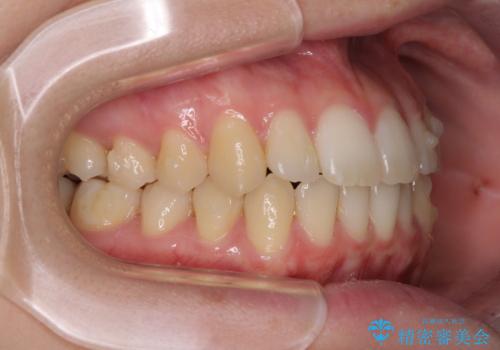

気になる前歯を整えたい インビザライン・ライトでの矯正治療

- ちょっとしたデコボコを整えたいとのことで来院された患者様です。

歯列不正は軽微であったため、インビザライン・ライトにより、費用を抑えて矯正治療を行うこととしました。

上下前歯の捻れが改善され、患者様には大変満足していただきました。